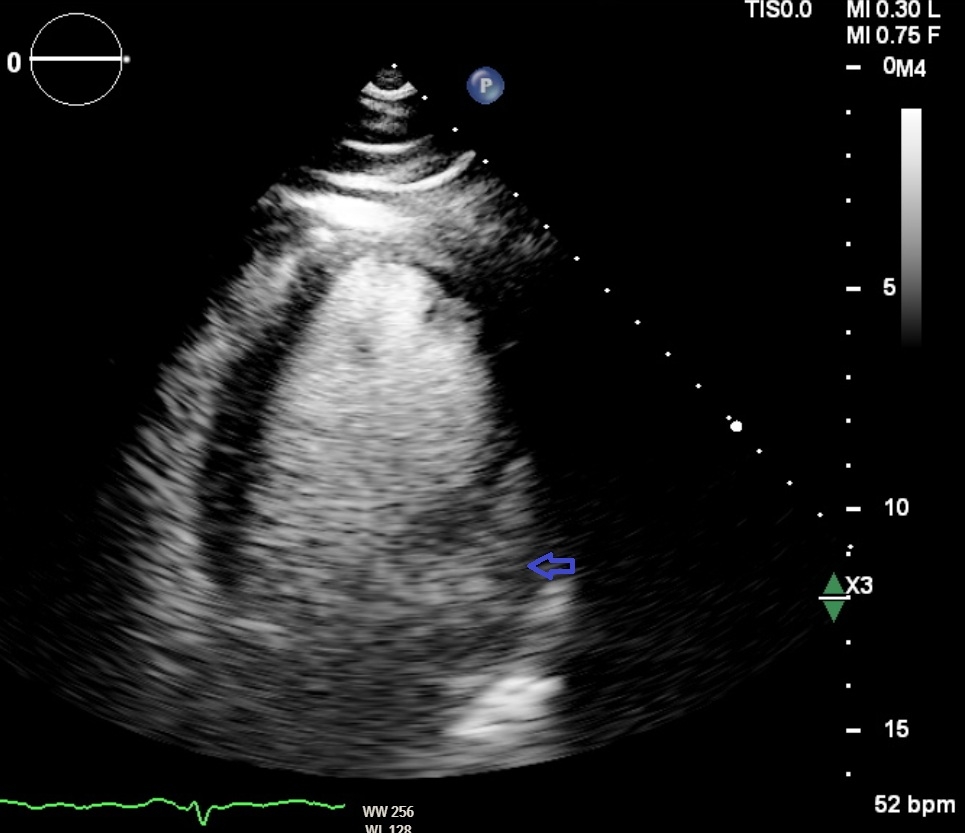

A 54-year-old Spanish-speaking male with no past medical history presented after being found unconscious and diaphoretic. Electrocardiogram demonstrated sustained monomorphic VT. After stabilization, transthoracic echocardiography revealed a left ventricular (LV) ejection fraction 30-35% with global hypokinesis and severely dilated LV cavity. Coronary angiography revealed patent coronaries. Further workup with cardiac magnetic resonance imaging demonstrated transmural late gadolinium enhancement in the basal to mid-lateral wall corresponding with hypokinetic myocardium, with a LV thrombus adjacent to the mitral valve and developing apicolateral aneurysm. An 18-fludeoxyglucose positron emission tomography scan was done which showed increased glucose uptake in the dysfunctional mid-lateral to apicolateral and anterolateral myocardium, without extracardiac evidence of sarcoid. Serologic testing was notable for an initially positive Lyme IgM, but confirmatory testing was negative. Further, serologies for Trypanosoma cruzi returned positive.